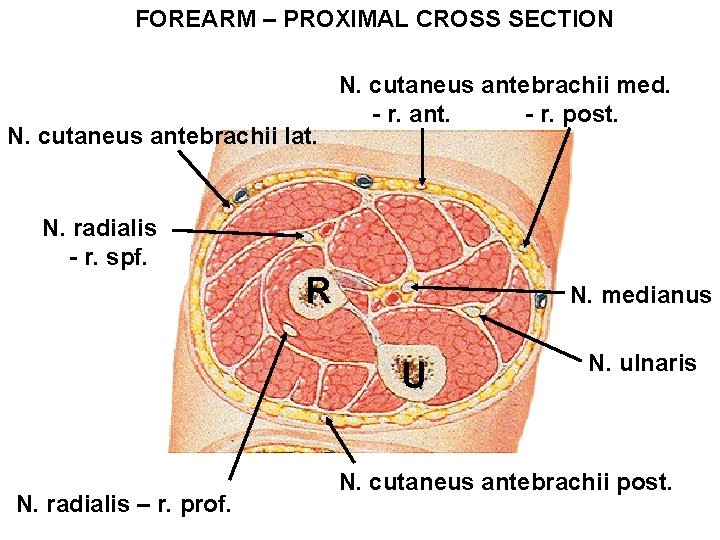

FOREARM – PROXIMAL CROSS SECTION N. cutaneus antebrachii lat. N. cutaneus antebrachii med. - r. ant. - r. post. N. radialis - r. spf. R N. medianus U N. radialis – r. prof. N. ulnaris N. cutaneus antebrachii post.